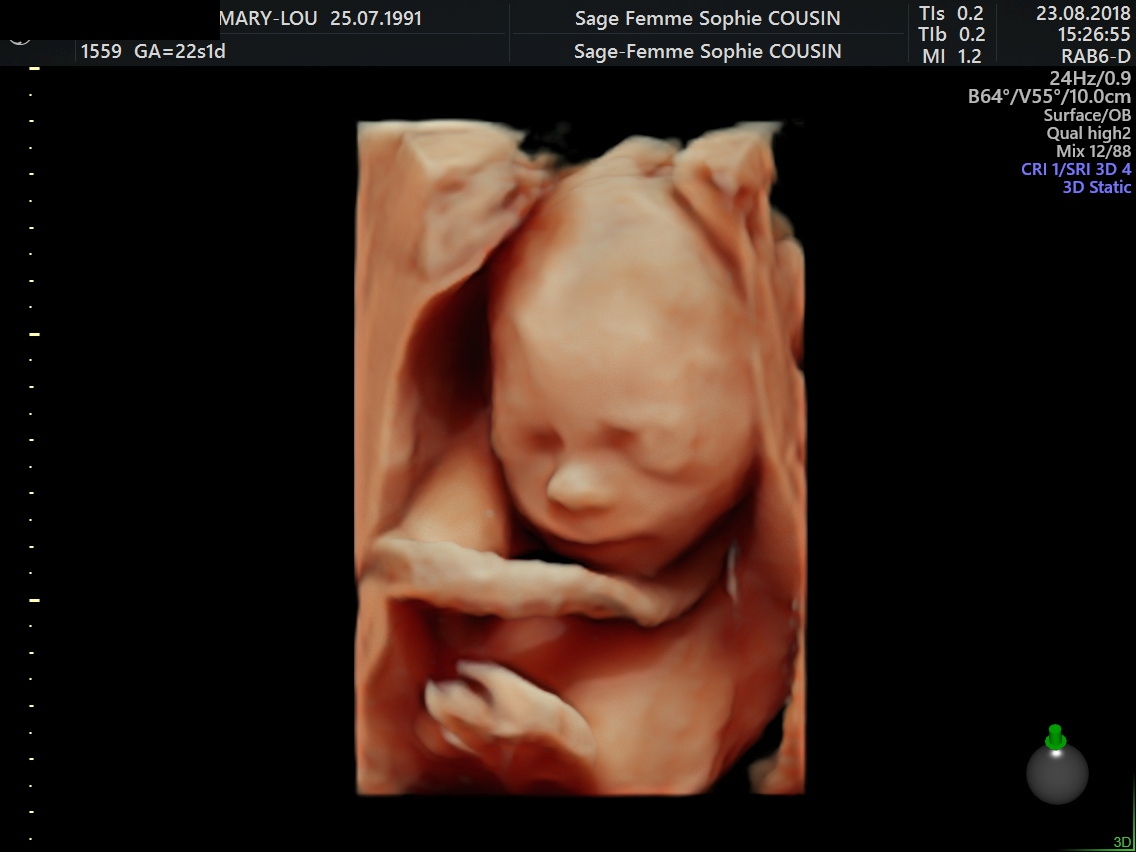

L'échographie se fait en première intention en 2D pour le dépistage. Nous utilisons également le 3D-4D dans certains cas et pour le plaisir des patientes (visualisation du visage) quand la position du fœtus le permet.

2-Echographie de 22sa

C'est une échographie très importante.

Elle a pour but de vérifier les organes du fœtus, l'absence de malformation , sa croissance, la position du placenta, le sexe du fœtus, la vitalité fœtale, la quantité de liquide amniotique.